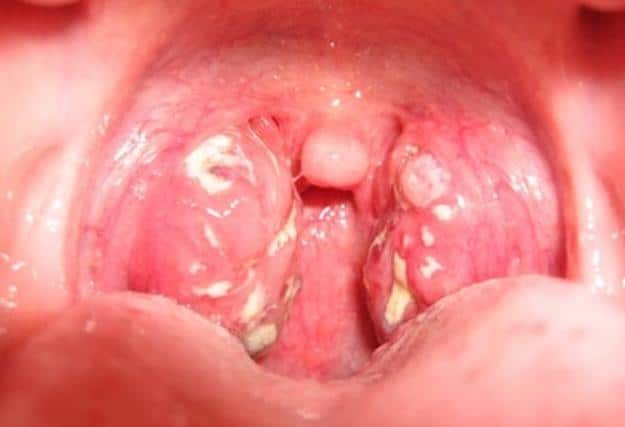

Аденоидные вегетации располагаются в задней части носоглотки, и их воспаление проявляется обильными слизистыми выделениями из носа. Аденоиды могут находиться по всей боковой стенке пазухи, на глоточных отверстиях и прикрепляться к своду носоглотки.

Носоглоточные миндалины имеют разнообразные формы и размеры.

Они прикреплены к носоглотке широким основанием и могут напоминать по форме гребень петуха.

Посередине эти образования разделены на несколько долек розоватого цвета.

На ощупь они обладают рыхлой структурой и имеют соединительные перегородки, между которыми располагаются лимфоциты.